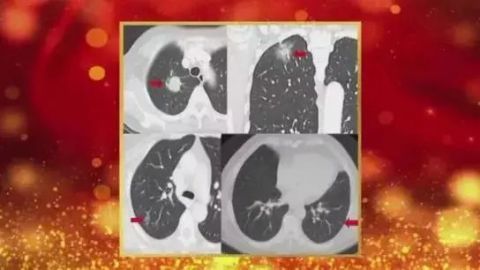

肺结节,在肺部影像表现为直径≤30mm的局灶性、类圆形、密度增高的实性或者亚实性肺部阴影,可为孤立性或多发性,不伴肺不张、肺门淋巴结肿大和胸腔积液。

根据胸部CT判断是否存在磨玻璃密度成分,可将肺结节分为:纯磨玻璃结节(PGGN)、实性结节和部分实性结节(PSN)。